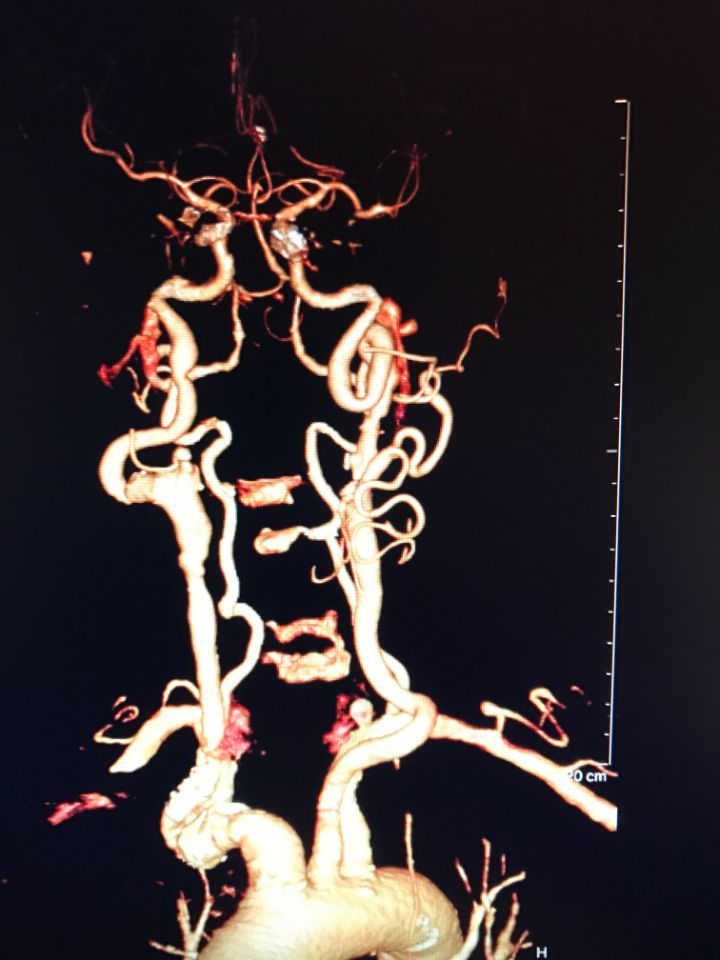

Ecco alcune immagini degli interventi eseguiti dal Dottor Viglione presso il suo studio a Cuneo.